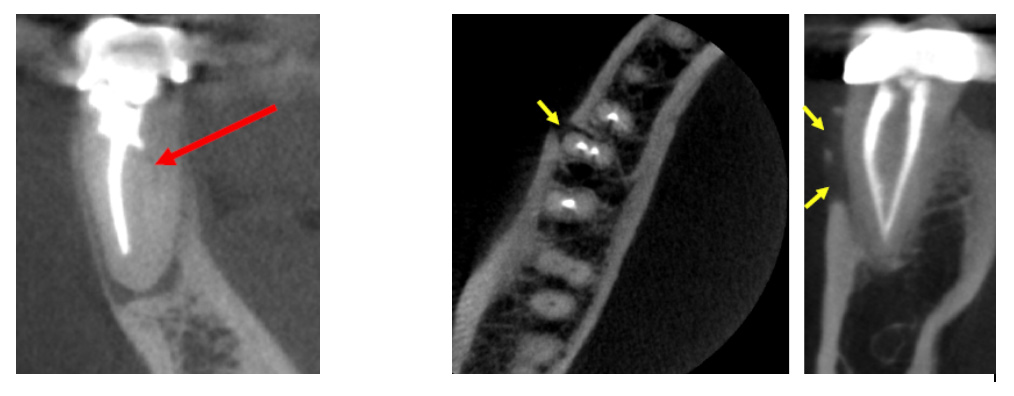

Clinical applications of CBCT technology in endodontics include the following:

Occasionally, dental defects or pathology that deem a tooth non-restorable will be revealed on a CBCT scan. If this happens, the endodontist will advise you that the tooth cannot be saved.

(Pictures of missed canal, vertical root fracture, extra tooth, and resorption)